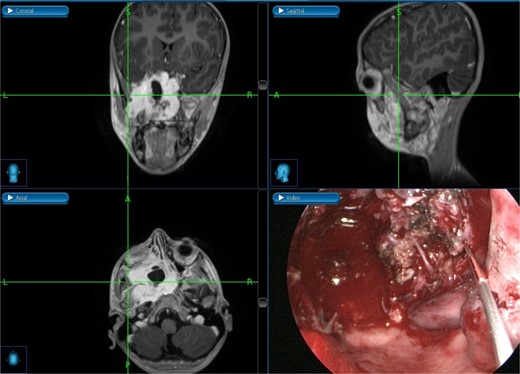

The patient underwent an endoscopic four-handed transseptal resection of the left JNA following uneventful embolization. Intraoperative endoscopic examination of the nasal cavity revealed a bluish mass in the left nasal cavity and a severe right-sided deviation of the nasal septum. A septal window was created, allowing bilateral access to the tumor. The tumor was dissected and removed, separating it from its bony attachments to the nasopharynx and clivus. Dissection extended to the bilateral sphenoid sinuses, allowing for complete tumor excision from the carotids, cavernous sinuses, infratemporal fossa, and skull base with navigation assistance (Fig. 2). The patient was asymptomatic on close follow-up until 8 months later, when he had intermittent self-limiting episodes of epistaxis without nasal obstruction. Examination revealed bilateral crustations and a small left nasal mass, with no obvious source of bleeding. Confirmation of tumor recurrence was done, and the patient underwent a successful second procedure for tumor resection.

Tumor dissection from the right ICA using intraoperative navigation assistance,with real-time display of instrument location in axial, coronal, and sagittal views.